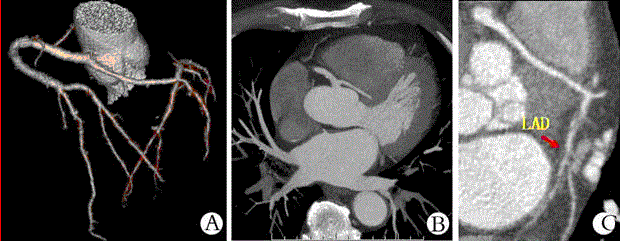

问题 下图所示的冠状动脉异常起源是

选项 A、右冠状动脉起源于主动脉左窦 B、左右冠状动脉共干 C、右冠状动脉异常起源于肺动脉 D、左冠状动脉起源于主动脉右窦 E、左冠状动脉异常起源于肺动脉

答案 B